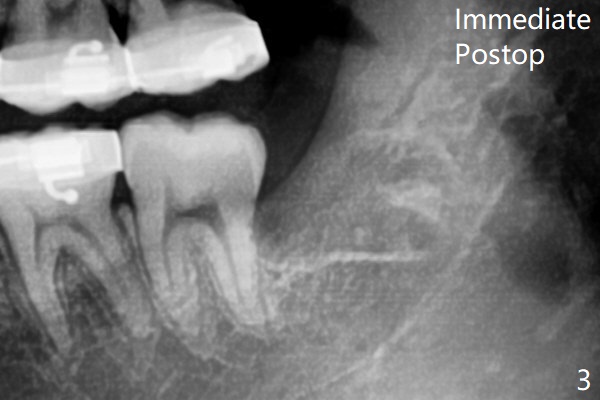

1.5年智齿牙根长长(图二)。1.5月后下颌智齿拔除放置Osteogen Plug(图三)。